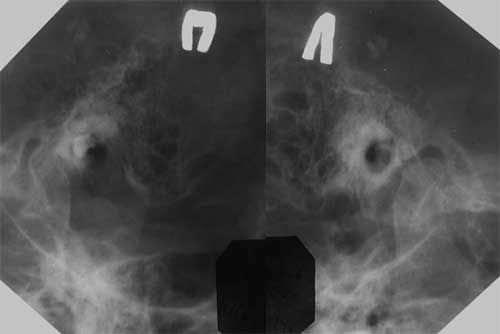

Рис. 2. Опухоль яремного гломуса. На рентгенограмме в проекции Шюллера разрушено дно барабанной полости справа.